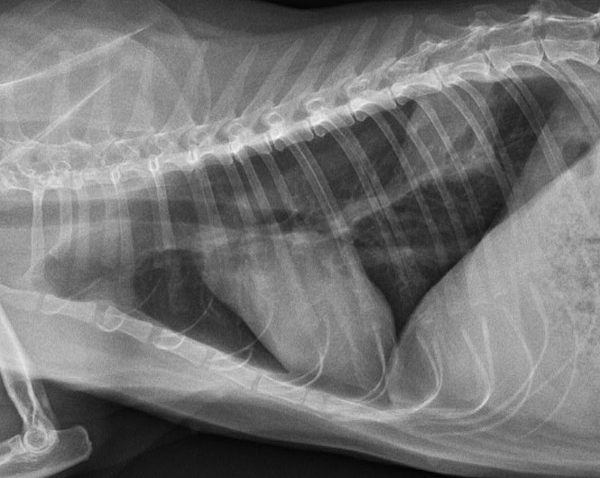

貓的肺部腫瘤

- Sep 15 Sun 2019 04:11